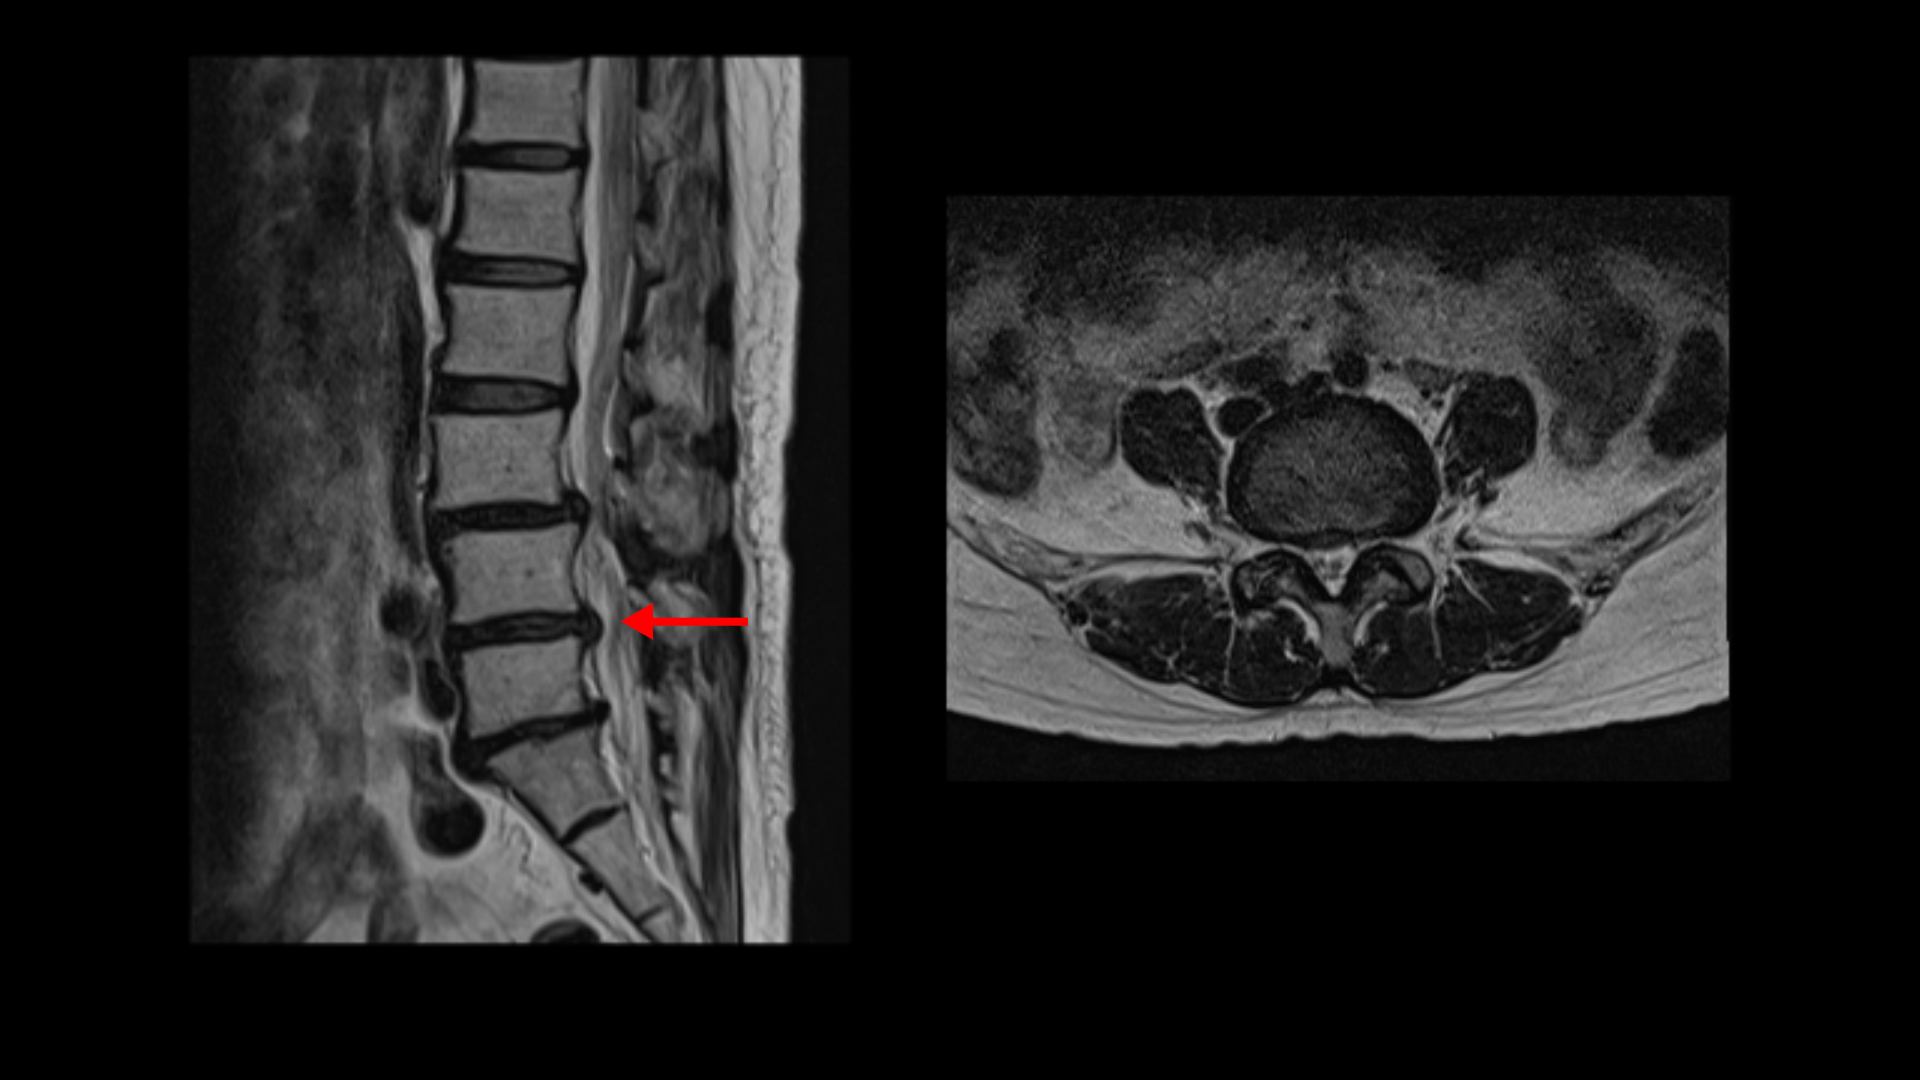

이분 MRI를 보면 3마디에 퇴행성디스크가 밀려 나와 있습니다.

또 3번 4번에는 척추전방전위증이 있습니다.

이 전방전위증 때문에 척추관에 중심성 협착도 있습니다.

4번 5번 디스크가 중앙에서 우측으로 약간 밀려 나와있고

>또 5번 1번에서는 신경이 빠져나가는 오른쪽 추간공이 약간 좁아져 있습니다.

이런 문제들 때문에 오른쪽 엉치부터 발가락까지 방사통이 있을 가능성이 있습니다. 하지만 어떤 마디가 정확한 통증의 원인인지 알기 어렵고 여러 마디가 안 좋기 때문에 이 환자분의 말씀을 들어봐도 전체적으로 여러마디 다 나사를 박자는 얘기를 들은 걸로 보입니다. 이렇게 여러 마디에 나사를 박는 유합술을 해놓으면 시간이 흘러 위나 아래에 문제가 생길 가능성도 커지고 환자분도 50대 초반의 젊은 나이라 대학병원의 교수님도 수술하기엔 너무 젊은 데라고 여러 번 말씀하셨다고 합니다. 그런데 신경 주사를 그토록 여러 번 오랜 시간 맞았는데도 환자가 심하게 아프면 수술 외에는 뾰족한 다른 방법이 없는 것이죠.

그런데 이분 허리 MRI를 자세히 보면 딱히 신경이 아주 극심하게 눌린 곳도 없습니다.

신경이 조금 눌릴 수는 있어도 심각해 보이지는 않습니다.

신경구멍이 지나가는 길이 여러 가지 퇴행성 변화로 조금씩은 좁아져 있지만 굳이 수술로 특히 여러 마디의 나사를 박는 수술까지 해가며 신경압박을 해소해야 할 정도의 심한 신경눌림은 보이지 않는 겁니다.